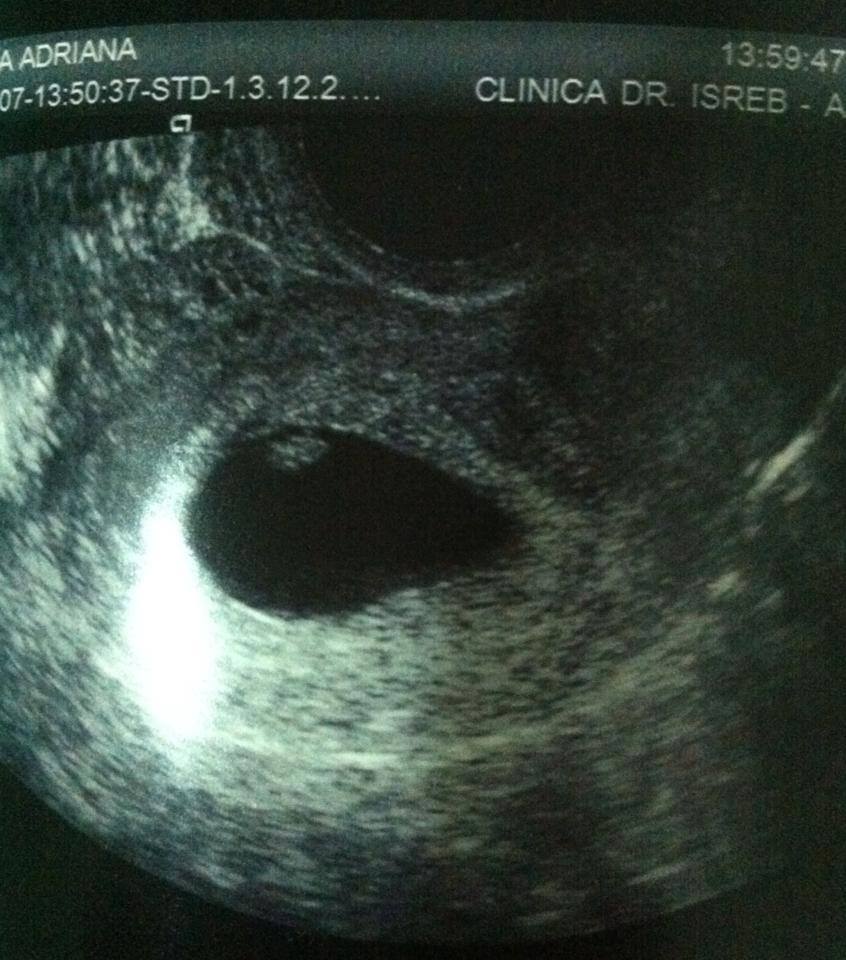

Fratele său, fotbalistul Costin Gheorghe, va deveni tătic. Acesta a postat pe contul personal o fotografie cu o ecografie, însoţită de un mesaj. Am primit cel mai frumos cadou de ziua mea!  Promit că voi fi un tata model pentru copilul meu! '', a scris plin de emoţii fratele artistei. Elena spunea cu ceva timp în urmă că îşi doreşte ca şi fratele ei să fie tătic, pentru că ţine foarte mult la sora sa Ana şi la el şi îşi doreşte ca şi ei să fie fericiţi ca şi ea.